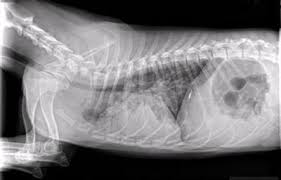

Lateral thoracic radiograph from a dog with a ventral alveolar pattern.

Lateral thoracic radiograph from a dog with a ventral alveolar pattern. That still leaves the question of why you should have recurrent pneumonia, unanswered and that is a question that will require further investigation. You can see on the left of the image a dark (relatively clear) lung. Pneumonia in people with lung cancer. The cause can be bacteria, a virus, or fungi. The problem here is that many things can enlarge the spleen above and beyond cancer. Note the increased soft tissue opacity in the lungs that partially obscures blood vessel margins. Various viruses, bacteria, and fungi can cause pneumonia. Differential diagnosis for common lung patterns in dogs and cats. I am a severe asthmatic and have had pneumonia on several occasions. This can happen when there is a high suspicion of cancer, for example, an enlarged spleen in a dog who is not acting right. Your veterinarian may recommend an fna and cytology or a biopsy, to confirm the diagnosis, and determine exactly what kind of lung cancer is present. Primary lung cancer are frequently located in the caudal (towards the hind end of the pet) lung lobes, however can be located in any lung lobe and are usually a single mass in the lungs, unless the tumor has spread.

Bacterial culture and drug sensitivity testing help the veterinarian to determine the best course of antibiotic treatment, if needed. His appetite is basically normal though his blood work shows that he is anemic. They did a cat scan and said the nod was.08 or 08 centimeters in dia. Note the increased soft tissue opacity in the lungs that partially obscures blood vessel margins. Bacterial pneumonia is an inflammation of the lung usually caused by bacterial or viral infection but can be caused by inhalation of an irritant. I am a severe asthmatic and have had pneumonia on several occasions. Your veterinarian may recommend an fna and cytology or a biopsy, to confirm the diagnosis, and determine exactly what kind of lung cancer is present. That still leaves the question of why you should have recurrent pneumonia, unanswered and that is a question that will require further investigation. The end stage of lung cancer in dogs is a very difficult time for dog owners as it's very hard to watch a beloved companion start giving up on life. Note the lobar sign with the caudal lung lobe. As these can also be caused by other disease, diagnostics include a full physical exam, blood work, radiographs, and may also require bronchoscopy with. A definitive diagnosis of lung cancer requires a sample of tissue (biopsy). This can happen when there is a high suspicion of cancer, for example, an enlarged spleen in a dog who is not acting right.